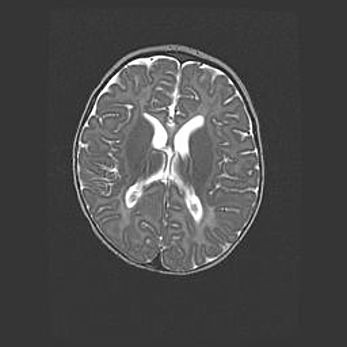

Множественные кисты обоих полушарий головного мозга, наибольшая из них в правой затылочной области. Ассиметричная атрофическая гидроцефалия.

Возраст: 7 месяцев

Вес: 5660 г

Пол: мужской

Окружность головы: 41,5 см

Срок гестации: 28-29 недель

Кисты головного мозга развиваются в результате многоочаговых некрозов вещества мозга и возникают вследствие перенесенной перинатальной инфекции, менингитов, энцефалитов, асфиксии, родовой травмы, расстройств мозгового кровообращения различного генеза. Образованию кист в веществе головного мозга плодов и новорожденных способствуют такие факторы, как высокое содержание в нем воды, недостаточная (или отсутствие) миелинизация и слабая астроглиальная реакция на повреждение.

Кисты могут сочетаться с гидроцефалией и другими поражениями головного мозга.